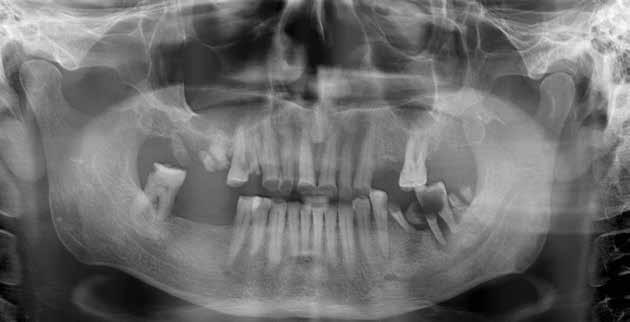

Alla visita di rivalutazione è emerso un ulteriore peggioramento della situazione, confermata anche dall’esame radiografico, con parodontopatia, sanguinamento al sondaggio, infiammazione diffusa, alitosi, difetto parodontale verticale mesiale a 2.3, residui radicolari 1.4, 1.6, 1.7, 3.6, 3.8 e carie destruenti di 1.5, 2.6, 3.5, 3.7 (con lesione endoperio) e 4.7 con estrusione e carie (Figg. 1, 2)

Il paziente, un uomo di 67 anni, ha confermato l’anamnesi precedente, ossia di essere portatore di

molteplici patologie: sindrome metabolica in discreto compenso farmacologico (riferita assunzione di metformina 500 mg, enalapril, acido acetilsalicilico, atorvastatina) e in terapia sostitutiva con levotiroxina perché operato di tiroidectomia totale per un tumore in giovane età; deambulazione autonoma con aiuto del bastone per via di un intervento al ginocchio abbastanza recente (riferito 6 mesi prima intervento di protesi totale di ginocchio).

Prima di procedere con gli interventi si è richiesto degli ematochimici di routine, per controllare soprattutto la glicemia, l’emoglobina glicata, la coagulazione, la vitamina D e i sali minerali.

Al controllo ematologico è emersa una emoglobina glicosilata molto superiore la percentuale accettabile a procedere (il valore era 9,3%) e deficit di D-25OH che è stato risolto con una terapia di ripristino con colecalciferolo 25000 U.I. Data la stretta correlazione tra emoglobina glicata e affezioni orali, è ormai routine seguire un percorso che porta alla bonifica della bocca e contestualmente, che aiuta il paziente anche con il controllo della glicemia. In prima battuta comunque, abbiamo sottoposto il paziente a una seduta orale. Per via del suo stato di salute (abbiamo stabilito per lui un rischio alto) durante ogni seduta invasiva abbiamo sempre monitorato il paziente con rilevazioni multiple dei parametri e reperendo un accesso venoso pe-

Dopo tre mesi dalla prima fase estrattiva sono stati ripetuti gli esami ematochimici dai quali l’emoglobina glicata del paziente è scesa a 7.2%. Abbiamo pertanto avviato con lo studio pre-implantare che prevede la ceratura diagnostica e gli esami radiologici più avanzati per scegliere i giusti impianti e la loro sede corretta.

L’esame CBCT ha rivelato un quantitativo di osseo sufficiente a procedere con l’intervento implantare, anche se erano ancora visibili le zone delle estrazioni; inoltre ha evidenziato una lesione osteolitica a carico del 3.5 che abbiamo dunque deciso di estrarre (Figg. 7-20).